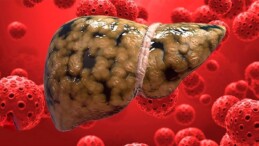

- SAĞLIK